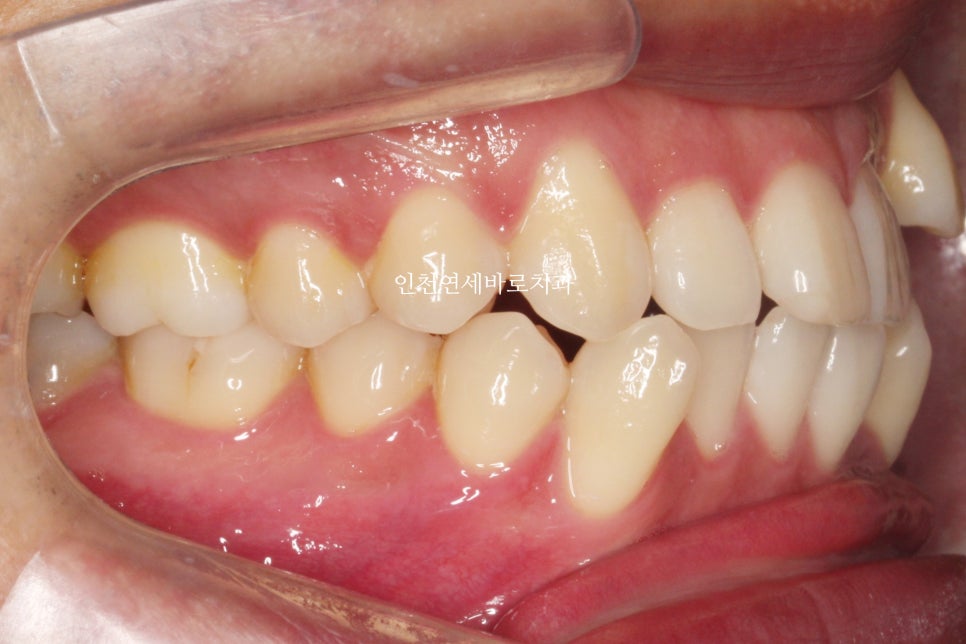

발치 교정으로 인비절라인 끝난 환자분으로

오른쪽은 그냥 돌출입의 교정

왼쪽은 덧니의 발치교정으로

좌 우를 보면 인비절라인과 관련된 모든 발치교정 이야기를 할 수 있을 것 같네요

약 7개월이 지난 후의 사진인데 벌써 많은 양의 덧니가 해결되었네요

약 1년 4개월이 지난 모습입니다.

치아의 배열이 확인됩니다.